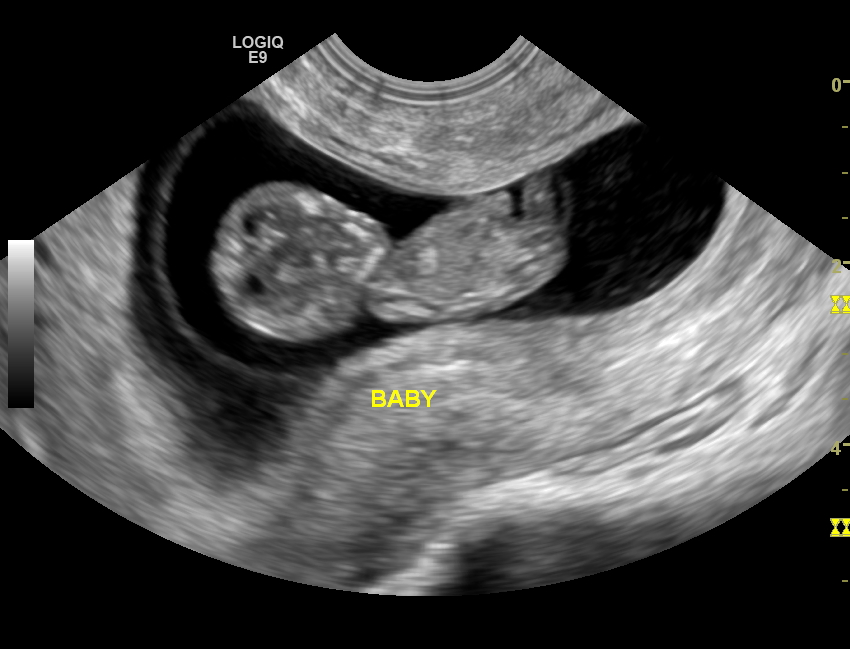

But pregnancy is a funny thing. When thinking about being pregnant (I thought I’d do it in my late twenties, early thirties) I thought to myself “I will be the healthiest prego ever.” I told myself, “You’ll eat like a saint, because you already do, you’ll exercise daily, because you already do and you will never touch refined sugars and processed foods because you barely do it now, why would you subject your baby to that crap” — Then, to my utter surprise this happened:

Oh did this little bundle of joy change my life. The day after I took the pregnancy test (around 6 weeks) I started the famous morning sickness. For me this was morning, noon, in-between, every second, even at night while I’m sleeping sickness. Oh, my every day coffee (WHICH I LIVED FOR) became my WORST nightmare. I literally could not think of anything on this planet that wanted to make me puke more than my morning coffee. Not only that but vegetables (my life, no seriously) made quiver in disgust, peanut butter (which I’d have every morning) was the devil, and all my whole grains (yep pasta, brown rice, whole grain bread…etc.) were completely off limits or off to the bowl I went (I did anyway even if I didn’t eat these things, but the thought of these items immediately made my tummy turn) , even my favorites like bananas were a no no. My food list consisted of white only things, white rice, white toast (plain NOTHING on it), the famous saltines, white potatoes (sweet potatoes, another fav was also out of the question), you get the picture…

Working on having a healthy pregnancy has been a challenge, which is weird to me because it is what I live… Healthy. But seeing my body change hasn’t been the easiest, yet feeling my little guy (yep! we are having a boy, Evan) doing flips reminds me that this is OK for now, and that someday I will be in full control of my body again but for now, I have a guest and he needs to be taken care of. So I take it day by day. I’m now into my 24th week of pregnancy and it has been a ride. Please continue to read… I promise there will be light hearted moments. 🙂

Here are some pictures!